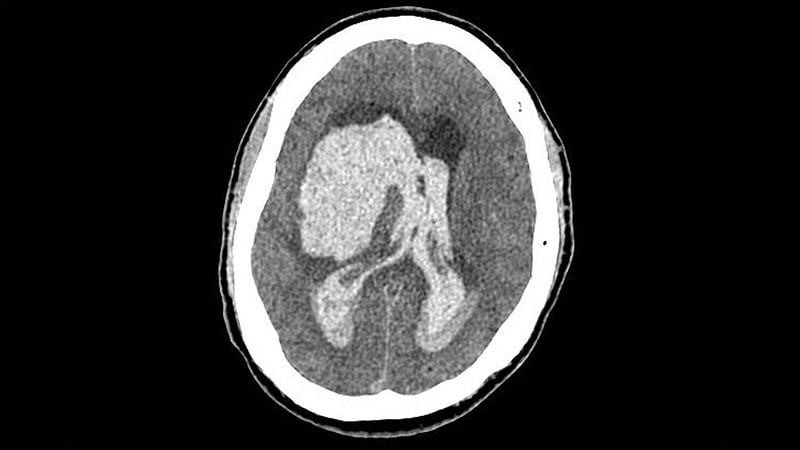

Improved Oral Anticoagulation for AF Patients with ICH: Promising Findings

New data from a meta-analysis of four small randomized trials and an ongoing study provide guidance on the use of oral anticoagulation in patients with atrial fibrillation (AF) who have had an intracranial hemorrhage (ICH). The meta-analysis showed that oral anticoagulation reduced the risk of ischemic major adverse cardiovascular events and ischemic stroke, but uncertainties about bleeding risk and small patient numbers prevented a definitive conclusion on net clinical benefit. The ongoing study, ENRICH-AF, reported an "unacceptably high risk of recurrent hemorrhagic stroke" in certain ICH patients receiving the anticoagulant being tested. Clinicians should weigh the risks and benefits on an individual basis, considering factors such as bleeding risk and stroke risk. Randomized trials are ongoing to provide clearer results in the future.